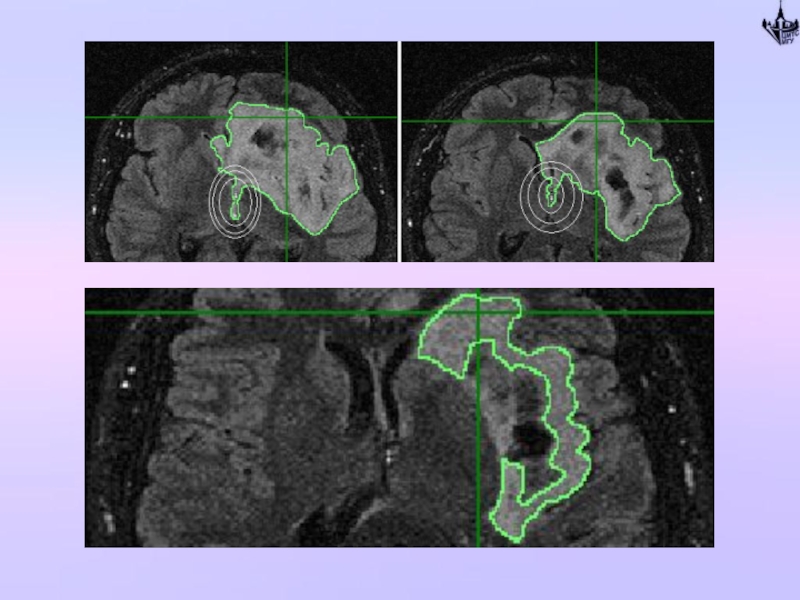

Слайд 57Практическая часть: сегментация зоны повышенного МР-сигнала

Слайд 59Практическая часть: сегментация зоны повышенного МР-сигнала

5) Разработан оригинальный алгоритм автоматической сегментации

для обработки МРТ-изображений, полученных с подавлением сигналов от нормальных тканей, который обладает широкими возможностями для подбора параметров сегментации, что позволяет его использовать в условиях слабого контраста и малого соотношения сигнал/шум.

6) Проведён расчёт динамики роста зоны поражения при астроцитоме за пятилетний период. Для расчета использованы изображения, полученные с подавлением сигналов от нормальной ткани. Для объемной обработки данных применён оригинальный алгоритм сегментации и разработанная в рамках задач данной дипломной работы методика коррекции артефактов.